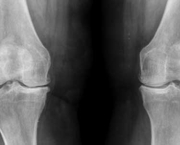

Além de considerar os sintomas relatados pelo paciente o médico pode solicitar exames como Raio-X das articulações que estão comprometidas. As radiografias simples são de grande utilidade nesses casos.